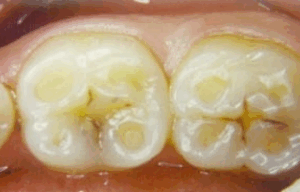

Enamel erosion, or tooth erosion, is a common problem that can occur at any age. The enamel surface of your tooth is dissolved and softened by contact with acids. These acids usually come from your stomach or from food and drinks.

Damage to the enamel from acid wear is irreversible and permanent so prevention is key!

What options do I have to fix damage already done by acid wear?

This will depend on the amount of damage done. Mild acid wear that is not getting worse can just be monitored with no treatment, however, moderate-severe cases may require full mouth rehabilitation in the forms of full coverage fillings or crowns. Best to talk to your dentist about your options.

Teeth which have acid wear are much more difficult to do fillings on because the quality of the enamel is poor. You are at a much higher risk of fillings not bonding and coming off/breaking.